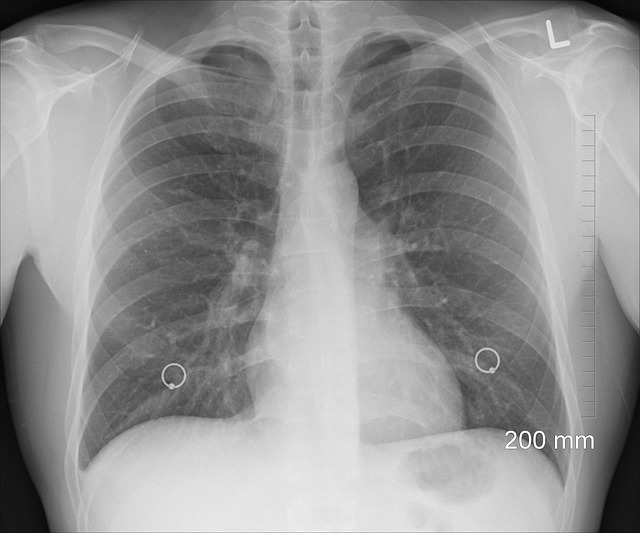

의료 영상 기술은 현대 의학에서 불가결한 부분으로 자리 잡고 있으며, 이는 물리학적 원리에 깊이 뿌리를 두고 있습니다. 이러한 기술들은 의사들이 인체 내부를 정밀하게 볼 수 있게 해주어, 정확한 진단과 효과적인 치료 계획 수립을 가능하게 합니다. X-레이, 컴퓨터 단층 촬영(CT), 자기 공명 영상(MRI), 그리고 양전자 방출 단층 촬영(PET)은 모두 물리학적 발견과 기술을 의료에 적용한 사례입니다.

X-레이는 전자기 스펙트럼의 일부로, 물체를 투과할 때 다른 밀도를 가진 조직에 따라 다르게 흡수됩니다. 이 차이를 이용해 뼈와 연조직 등 인체 내부 구조의 이미지를 생성합니다. X-레이는 골절이나 폐 질환 같은 상태를 진단하는 데 특히 유용합니다.